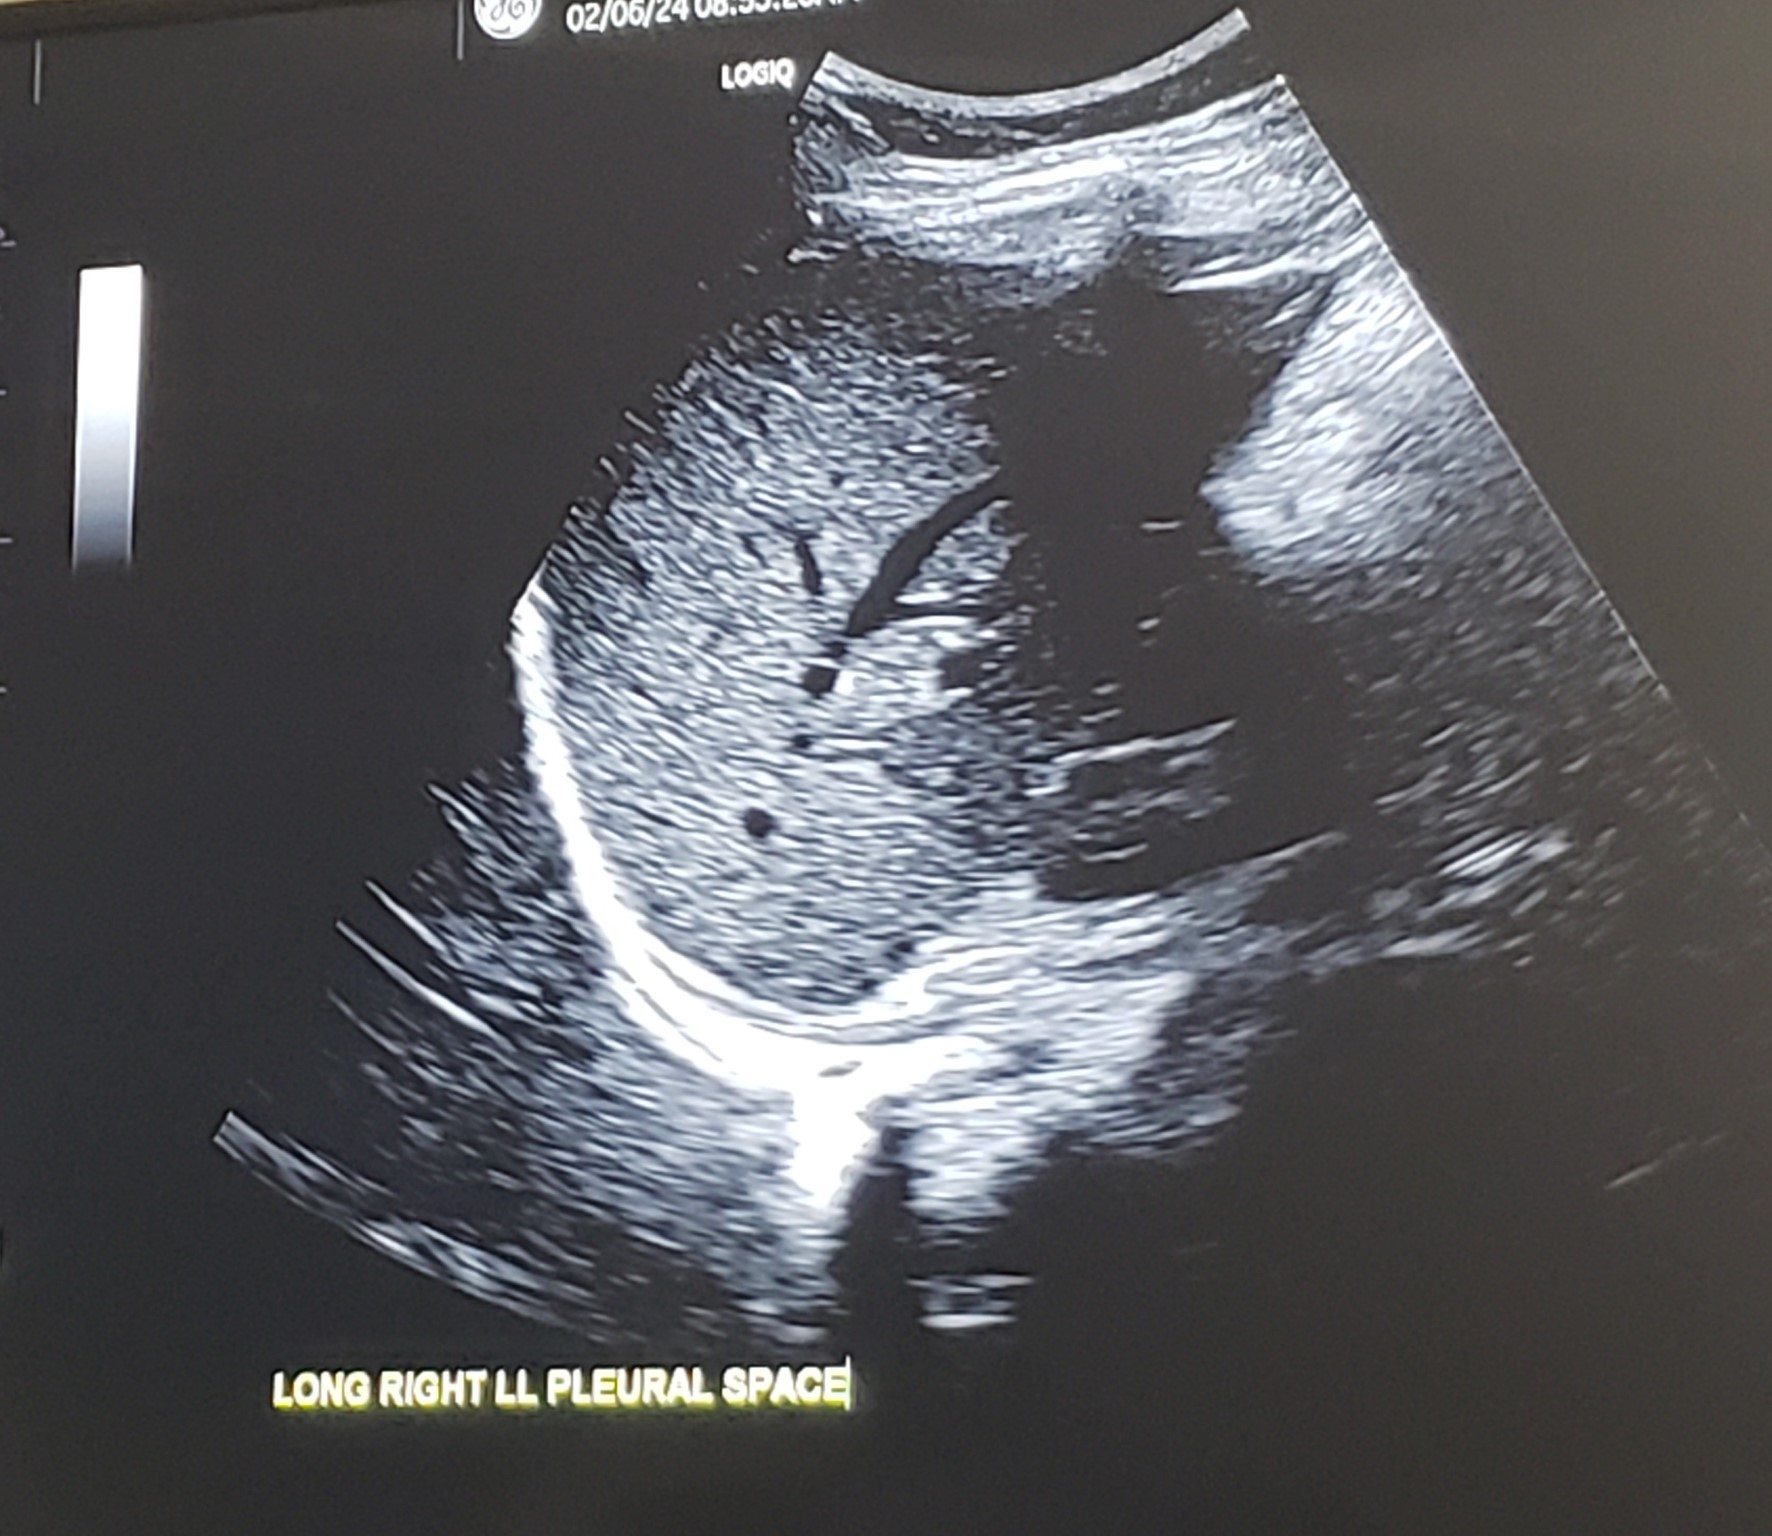

Sag./Long Rt. Pleural Space